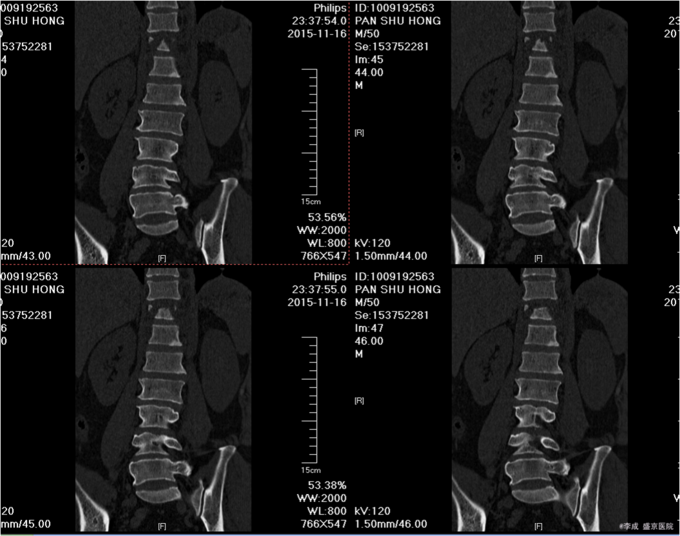

5.专科查体: 患者双上肢活动可,感觉正常 。两侧腹股沟韧带中点连线以下皮肤感觉消失。双下肢肌力均为0级,上臂肌力(R5,L5),前臂肌力(R5,L5),手掌掌屈肌力(R4,L4),手掌背伸肌力(R4,L4)。双手握力(R4,L4)。髂腰肌肌力(L0级,R0级),伸膝力(L0级,R0级),足背伸力(L0级,R0级),足跖屈肌力(L0级,R0级),神经反射:BCR:L(++)R(++),TCR:L(++)R(++),肱桡肌反射:(++)R(++),PSR: L(++++)R(++++),ASR: L(++++)R(++++),Hoffmann Sign:L(-)R(-), Babinski Sign L(-)R(-) 双侧桡动脉足背动脉可扪及搏动,末梢血运良好. 辅助检查:腰椎椎CT平扫+三维(2015-11-16,本院):胸11椎体向前滑脱,胸12椎体压缩性骨折,椎管改变,建议MR检查。 左侧第12后肋骨折。 腰1左侧横突骨折不除外。。